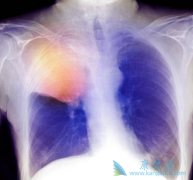

帕博利珠单抗对比多西他赛在PD-L1>50%的患者中均能延长总生存期

KEYNOTE-010研究是一项全球、开放的II-III期研究,在PD-L1 TPS ≥1%的经治晚期非小细胞肺癌(NSCLC)患者中评估了 帕博利珠单抗 10 mg/kg或2 mg/kg Q3W vs 多西他赛。在中位随访13.1个月后的分析结果显示,帕博利珠单抗对比多西他赛在PD-L1 TPS ≥1%和≥ ...